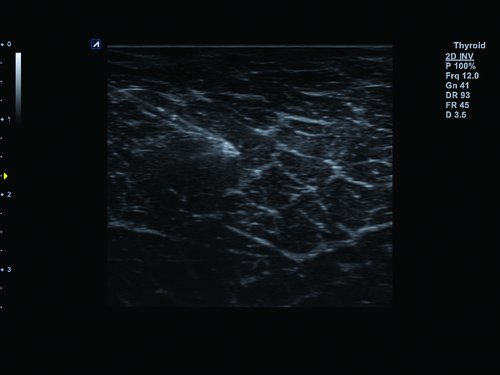

• Kleine Organe

• L3-12T (3-12 MHz) für Ultraschalluntersuchungen in Bereichen Brust, Notfallmedizin, MSK, Vaskulär, Kleine Organe, Appendix

• Advanced Speckle Reduction Imaging. Filtertechnologie zur Minimierung der Artefakte und Verbesserung der Definition der Gewebegrenzen

• Filtered Tissue Harmonic Imaging: Bilder mit verbesserter Kontrastauflösung und deutlich reduziertem Rauschen durch Analyse der harmonischen Oberwellen